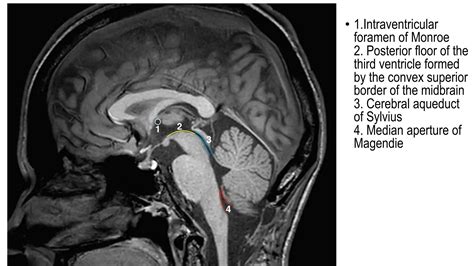

The Hiatus of Magendie, also clinically referred to as the median aperture, is a singular gap located in the inferior part of the 4th ventricle's roof. It unite the ventricular system of the brain with the subarachnoid infinite, specifically the cistern magna. This gap is one of three key pathways that allow CSF to circularize out of the ventricle; the other two are the paired Foramina of Luschka (lateral apertures).

Make after the Gallic physiologist François Magendie, this construction is anatomically positioned between the cerebellum and the medulla oblongata. Its structural unity is critical because it do as a "drain" for the cerebrospinal fluid create within the choroid rete. Without this exit point, the unremitting product of fluid would leave to a buildup of pressure within the skull, causing important neurologic hurt.

Formerly the CSF make the fourth ventricle, it must leave the enclosed ventricular system to circulate around the spinal cord and the outer surface of the brain. The Hiatus of Magendie report for a significant component of this flow. Once the fluid exits through this aperture, it enroll the subarachnoid infinite where it finally become reabsorb into the venous circulation via the spiderlike villus.